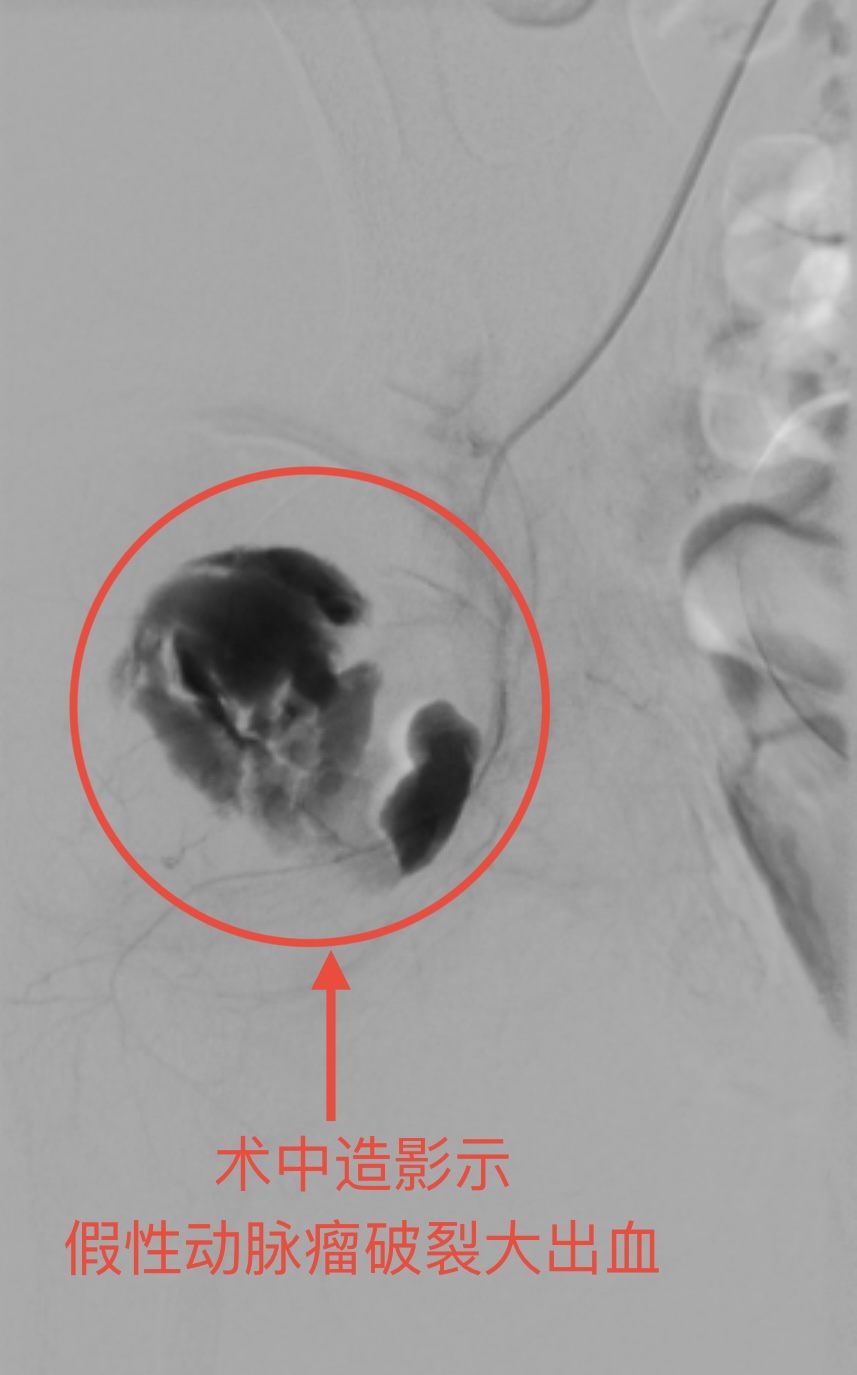

3月18日,骨科团队为小星进行了骨折切开复位内固定等一系列手术。3月26日中午,小星右侧臀部突然大出血,检查发现是右侧髂内动脉假性动脉瘤破裂。若不及时处理,随时可能因失血过多导致死亡。

血管外科主任李良学接到通知后,第一时间奔赴导管室,决定采用经皮DSA经导管髂内动脉栓塞术精准堵住出血点。导管室内,在DSA的引导下,李良学双手稳稳地操作着导管穿过错综复杂的血管,准确抵达出血点,将弹簧圈顺利置入,成功堵住了破裂的动脉。